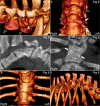

Background: Computed tomography (CT) is used to evaluate body composition and limb osteochondrosis in selection of breeding boars. Pigs also develop heritably predisposed abnormal curvature of the spine including juvenile kyphosis. It has been suggested that osteochondrosis-like changes cause vertebral wedging and kyphosis, both of which are identifiable by CT. The aim of the current study was to examine the spine from occiput to sacrum to map changes and evaluate relationships, especially whether osteochondrosis caused juvenile kyphosis, in which case CT could be used in selection against it. Whole-body CT scans were collected retrospectively from 37 Landrace or Duroc boars with poor back conformation scores. Spine curvature and vertebral shape were evaluated, and all inter-vertebral, articular process and rib joints from the occiput to the sacrum were assessed for osteochondrosis and other lesions.

Results: Twenty-seven of the 37 (73%) pigs had normal spine curvature, whereas 10/37 (27%) pigs had abnormal curvature and all of them had wedge vertebrae. The 37 pigs had 875 focal lesions in articular process and rib joints, 98.5% of which represented stages of osteochondrosis. Five of the 37 pigs had focal lesions in other parts of vertebrae, mainly consisting of vertebral body osteochondrosis. The 10 pigs with abnormal curvature had 21 wedge vertebrae, comprising 10 vertebrae without focal lesions, six ventral wedge vertebrae with ventral osteochondrosis lesions and five dorsal wedge vertebrae with lesions in the neuro-central synchondrosis, articular process or rib joints.

Conclusions: Computed tomography was suited for identification of wedge vertebrae, and kyphosis was due to ventral wedge vertebrae compatible with heritably predisposed vertebral body osteochondrosis. Articular process and rib joint osteochondrosis may represent incidental findings in wedge vertebrae. The role of the neuro-central synchondrosis in the pathogenesis of vertebral wedging warrants further investigation.